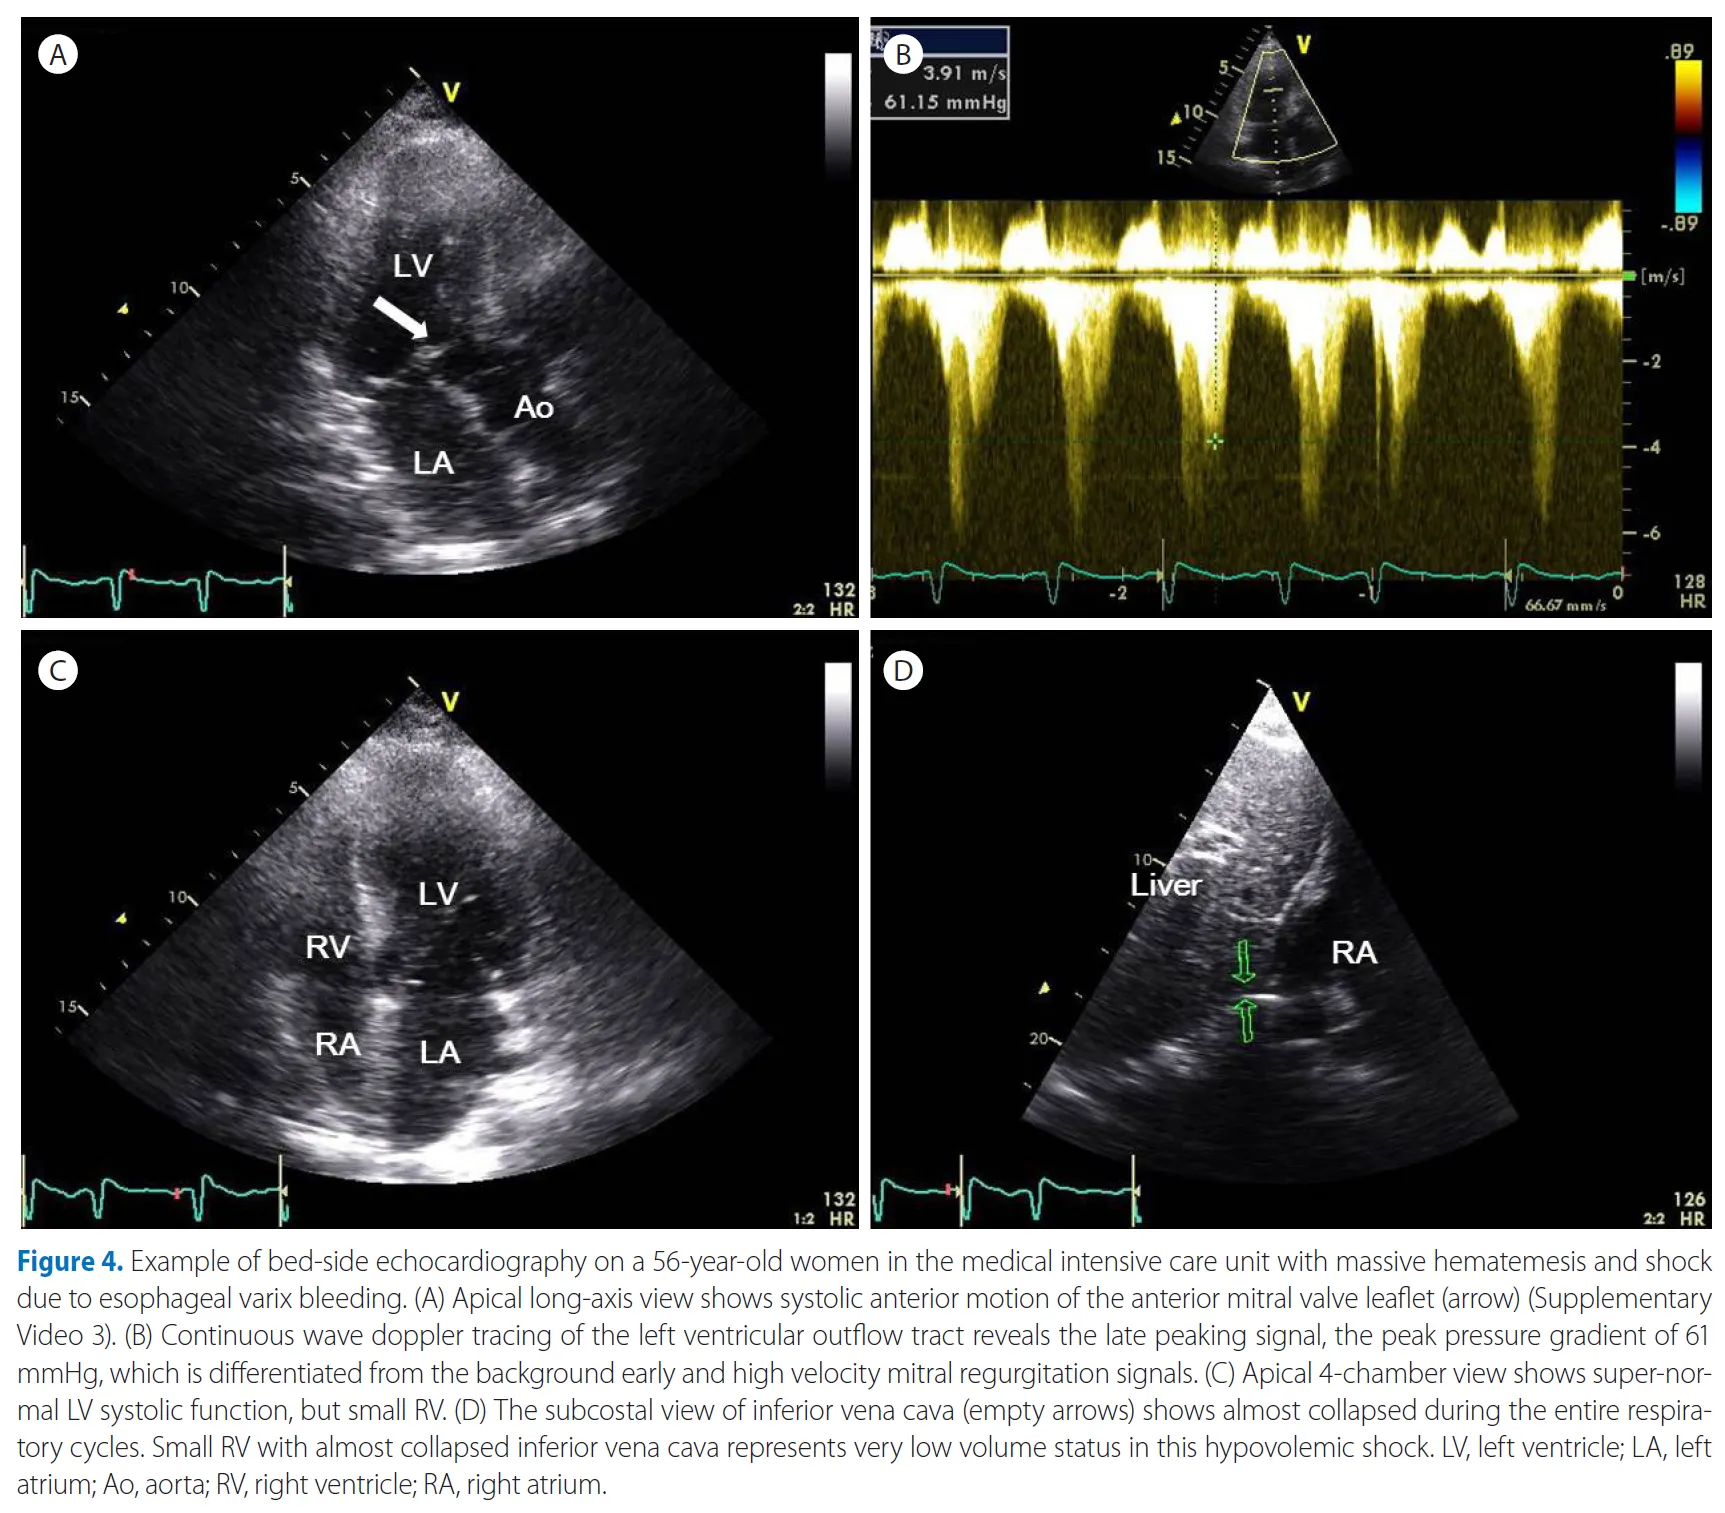

승모판 전엽의 수축기 전방 이동과 더불어 발생되는 좌심실 유출로 압력 차를 평가

: dynamic obstruction 존재에 따라, 혈관 내 볼륨을 정주하고, 오히려 도파민과 같은 약제를 끊게 되는 판단의 근거를 제공하므로, 치료적 측면에서 중요한 평가 도구라 할 수 있다.

식도 정맥류 출혈로 인한 다량의 출혈과 쇼크로 중환자실에 입원한 56세 여성의 침대 옆 심초음파 검사 예시입니다.

식도 정맥류 출혈로 인해. (A) APLX view는 전방 승모판 전단(화살표)의 수축기 전방 운동을 보여줍니다. (B) 좌심실 유출로의 CW 도플러 추적은 Late peaking signal, 즉 최고 압력 구배 61 mmHg로, 배경의 초기 및 고속 승모판 역류 신호와 구별됩니다. (C) AP4C view는 super-normal LV systolic function 을 보여주지만, RV는 작다. (D) 하대정맥의 늑골 하보기 (빈 화살표)는 전체 호흡기 동안 거의 붕괴 된 것을 보여줍니다. 거의 collape된 IVC와 작은 RV는 이 저혈량성 쇼크에서 매우 낮은 체적 상태를 나타냅니다.